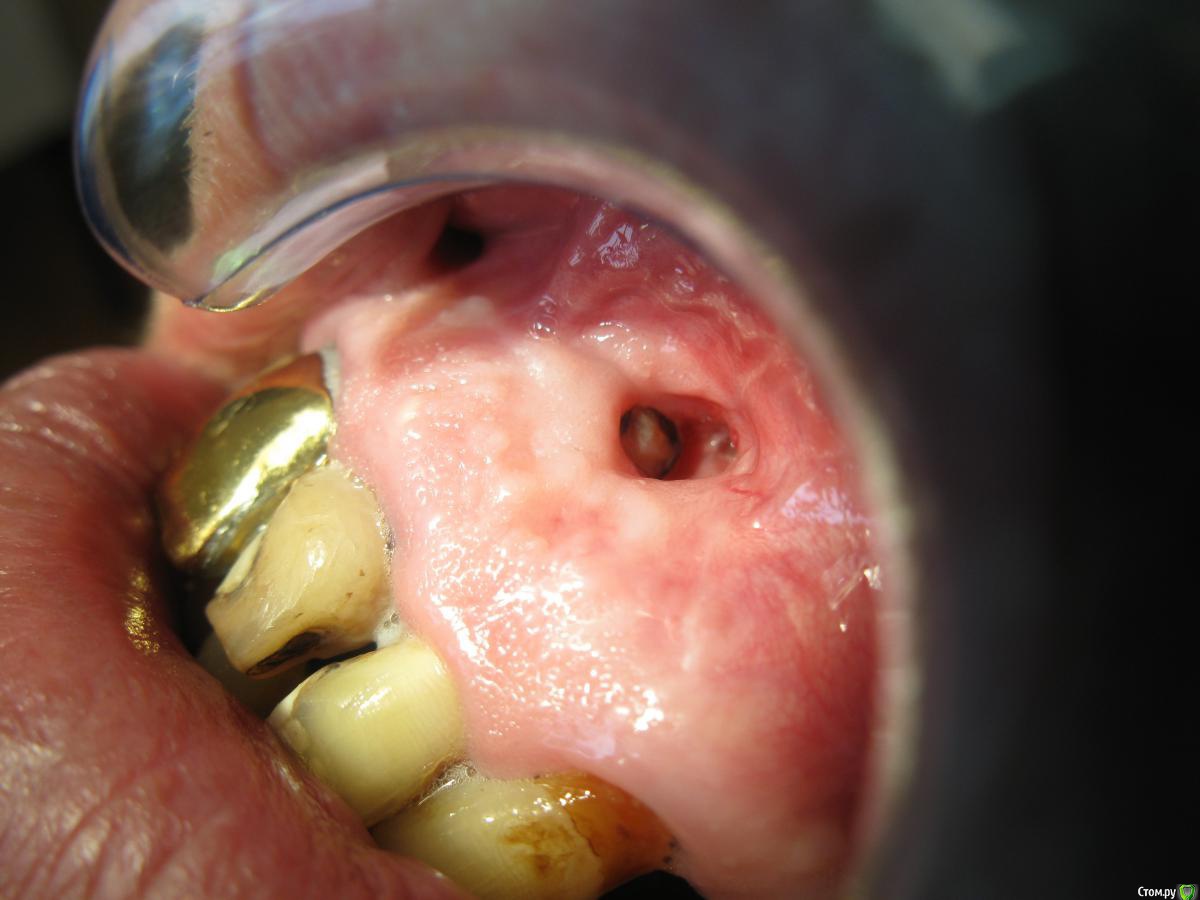

Iwan Опубликовано 6 июня, 2017 Поделиться Опубликовано 6 июня, 2017 Доброго времени суток! Обратился пациент, спустя примерно 1 месяц, после цистэктомии 21 зуба. Жалуется на дискомфорт под верхней губой, но боли нет. При осмотре я увидел с вестибулярной поверхности в проекции апекса 21 зуба кистозную полость диаметром примерно 5мм, выстланную слизистой и торчащий апекс корня 21. Я пробовал это лечить по принципу цистотомии, то есть два раза в неделю менял йодоформные турунды, прошло два месяца, улучшения минимальные.Отправил я его туда где он делал операцию, там сказали продолжать такое лечение еще около 3 месяцев. Я вот думаю может перекрыть лоскутом, но не знаю как его правильно сформировать. Может есть у кого какие предложения и советы? Ссылка на комментарий

Iwan Опубликовано 9 июня, 2017 Автор Поделиться Опубликовано 9 июня, 2017 Опыта в фото нет, не судите строго) Ссылка на комментарий

Iwan Опубликовано 9 июня, 2017 Автор Поделиться Опубликовано 9 июня, 2017 Снимок он не взял, а новый делать не захотел, торопился на работу Ссылка на комментарий